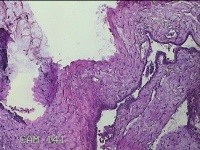

右侧卵巢囊肿

性别

女

年龄

36岁

临床诊断

一般病史

发现双侧附件囊肿1年。

标本名称

大体所见

灰白暗红色囊壁样组织2.5x2x0.3cm一块,表面光滑,部分已切开,囊内容物已流失,囊壁厚0.2cm。

考虑:子宫内膜异位囊肿。